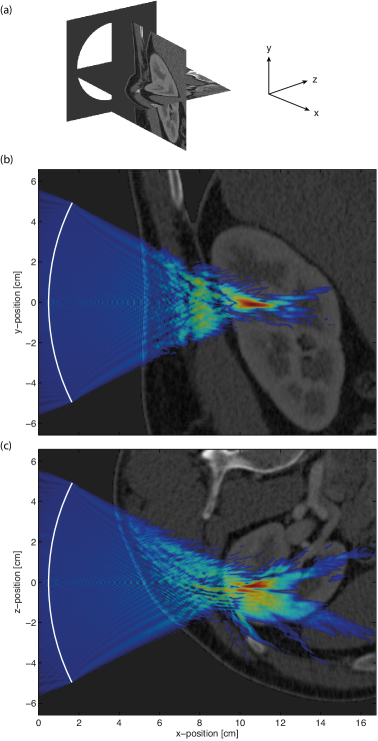

To illustrate the utility of the developed nonlinear ultrasound model for solving real-world problems, a complete large-scale nonlinear ultrasound simulation representing a single HIFU sonication of the kidney was performed. The medium properties for the simulation were derived from an abdominal CT scan (the MECANIX dataset available from http://www.osirix-viewer.com/datasets/). This was resampled using linear interpolation to give the appropriate resolution. The density of the tissue was calculated from Hounsfield units using the data from Schneider et al. [52], and the sound speed was then estimated using the empirical relationship given by Mast [57]. The remaining material properties were assigned book values [44]. The HIFU transducer was defined as a circular bowl with a width of 10 cm and a focal length of 11 cm. The shape of the transducer within the 3D Cartesian grid was defined using a 3D extension of the midpoint circle algorithm [54]. The transducer was positioned behind the patient as shown in Fig. 8(a), and was driven at 1 MHz by a continuous wave sinusoid. The acoustic intensity at the transducer surface was set to 2 W/cm2 to simulate a treatment that would likely operate largely in a thermal regime (i.e., with minimal cavitation). Outside the body, the medium was assigned the properties of water [44]. The total domain size was 17 cm 14.3 cm 14.3 cm and the grid spacing in each Cartesian direction was set to 93 m, giving a total grid size of 2048 1536 1536 grid points and a maximum supported frequency of 8 MHz (i.e., eight harmonics of the source frequency). The simulation length was set to 220 with a CFL number of 0.18, giving a total of 19800 time steps. Simulations of this scale and complexity have not previously been possible.

The simulation was executed using 768 cores on VAYU with seven checkpoint-restart stages. The total wall-clock time was 31 hours and 20 minutes, and the total memory used was 780 GB. The compressed input file was 45 GB, while the output file was 450 GB. This comprised 36 GB to store the peak positive and peak negative pressure across the domain, and 414 GB to store the time varying pressure and particle velocity for 6 periods in steady state over a 45 mm 30 mm 30 mm region surrounding the HIFU focus. Transverse and sagittal slices through the peak positive pressure overlaid onto the corresponding CT data used to define the material properties are shown in Fig. 8(b)-(c). The distortion of the ultrasound focus due to the body wall and the fat layer surrounding the kidney is clearly visible. These effects have been noted clinically, and remain a barrier to the application of HIFU in the kidney [58]. Thus, one possible future application of the developed -space model would be a systematic investigation into the conditions necessary for viable HIFU ablation in the kidney (for example, the maximum thickness of the fat layer). In any case, the example serves to illustrate the utility of the implementation.